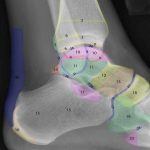

Giải Phẫu X-Quang Chi Dưới | Bài giảng CĐHA

* Giải phẫu X-quang chi dưới: Khung chậu – Khớp háng – Xương đùi – Khớp gối – Cẳng chân – Cổ chân – Bàn chân.